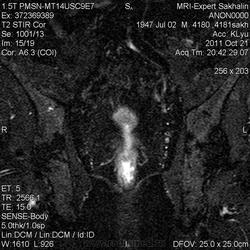

Сегодняшний пациент направлен врачом Онкодиспансера-как обычно без документов, выписок , результатов исследований)))Перенес операцию по удалению опухоли прямой кишки , наложена колостома.

Зато вопросы в направлении:1Протяженность опухоли.2.Depositae in hepar.3Мезоректум.При этом назначил только малый таз....

Прошу помощи!Во-первых, не совсем понятная простата и мочевой пузырь; на некоторых сканах есть признаки тесного прилежания простаты к стенке кишки.В общем-я ничего не понимаю-что удалили!

Признаков распространения опухоли в мезоректум я не вижу (наружный контур кишки четкий, ровный), простата и апоневроз Денонвилье интактны. А в мочевом скорее всего утолщенная межмочеточниковая складка попала в срез .Элевация простаты в мочевой пузырь? Нужны короналы с мочевым пузырем и ПЖ.

Ольга Сергеевна, я завтра у направляющего врача узнаю.Простата гиперплазирована, но прорастания достоверно не вижу.Мезоректум, кажется, тоже интактен.Спасибо за комментарий!